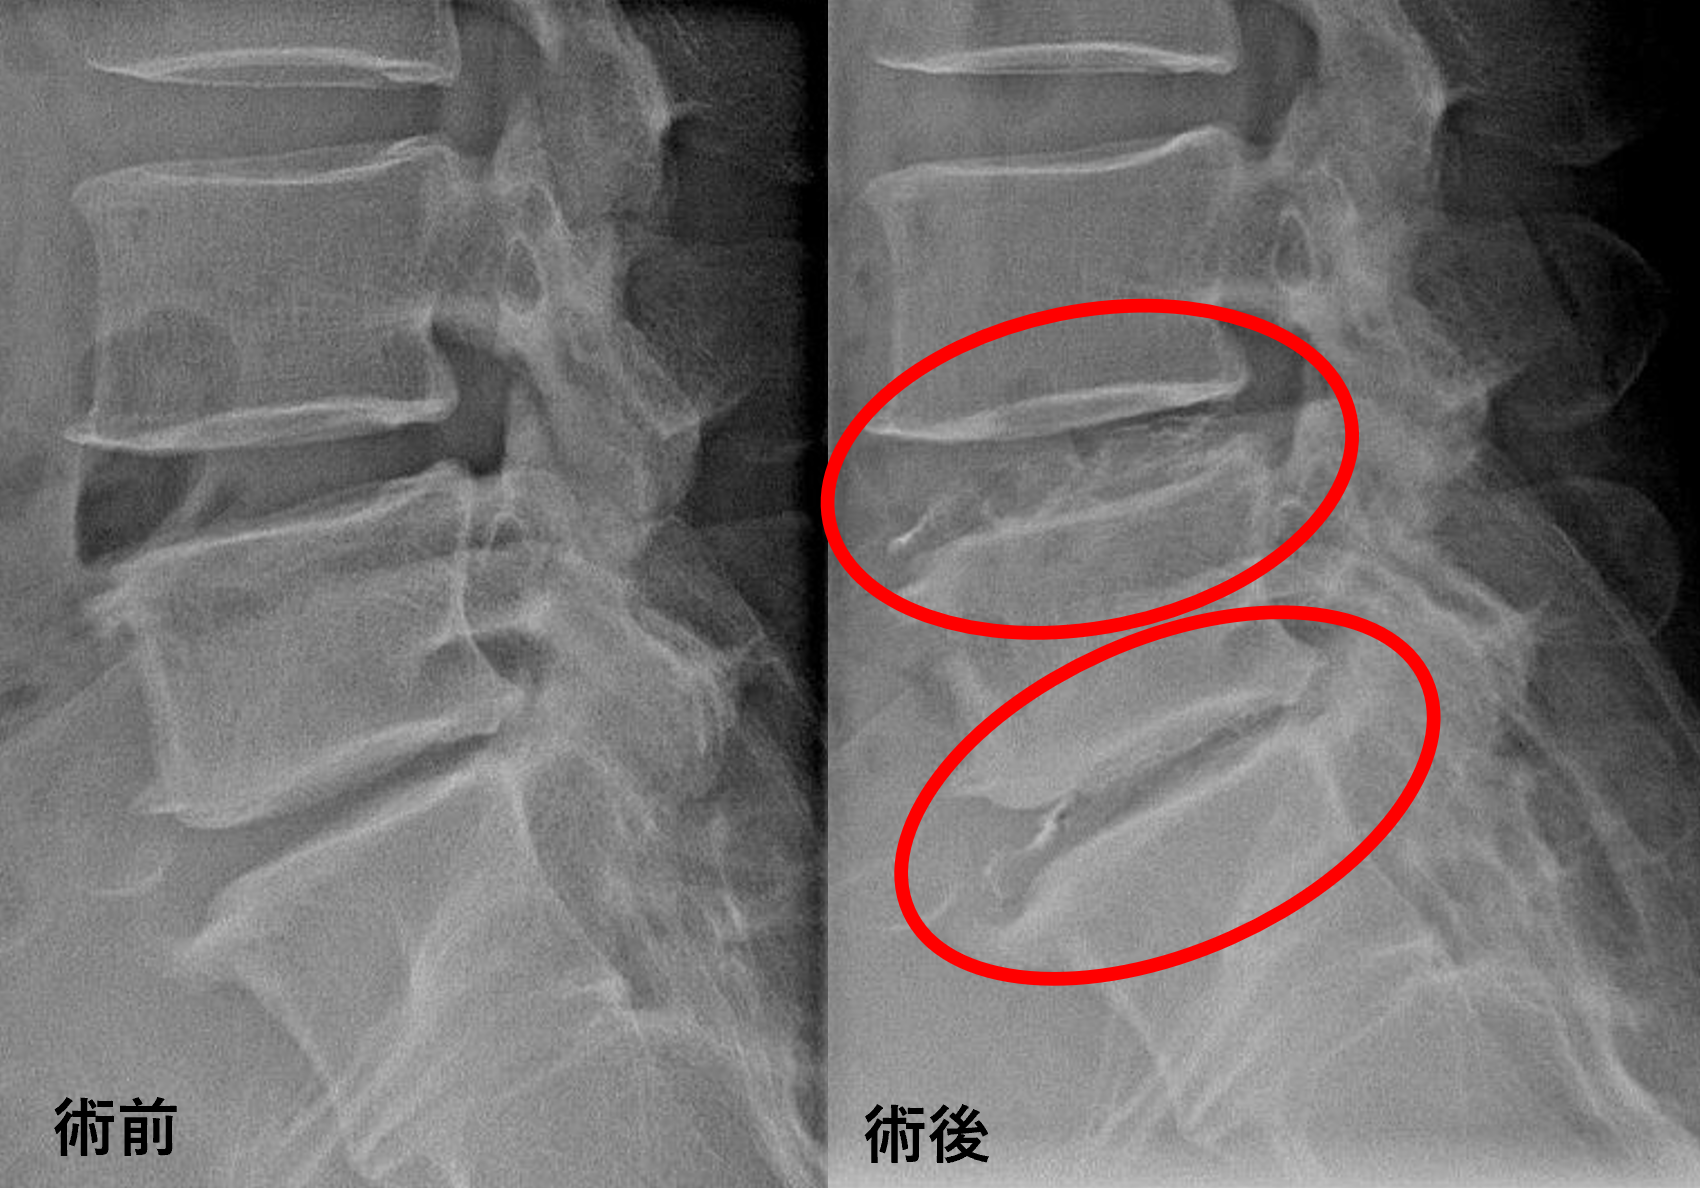

患者様と相談の元、L4/5、5/sにセルゲル法を施行

治療は小原医師が行いました。

治療は30分程度で終了

回復室で休憩後、歩いて帰院されました。